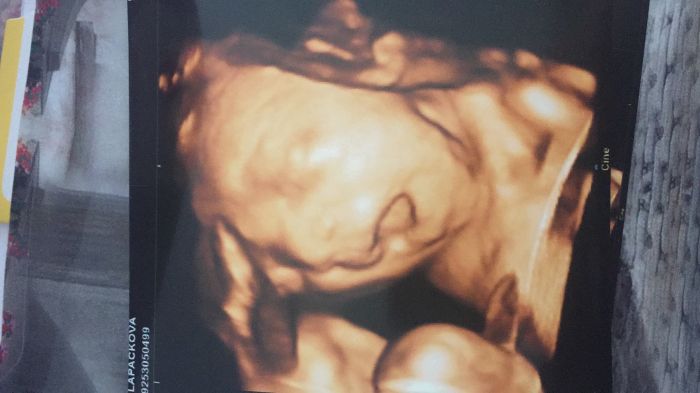

Holky tak Vám jdu ukázat toho našeho krasoně ❤️ pani doktorka na 4D byla úžasná mam asi 8fotek hezky nám k tomu povídala pustila nám i srdíčko..jen ten náš prďola se furt vrtěl vrtěl a pak se schovával a tak mi dala ještě jeden termín za 14 dní že to zkusíme znovu jestli se malej umoudří,ale u tak jsem nadšená a můžu jedině doporučit :)

Ahoj Káč, to je opravdu vtipnej obrázek. Vypadá, jako když zpívá